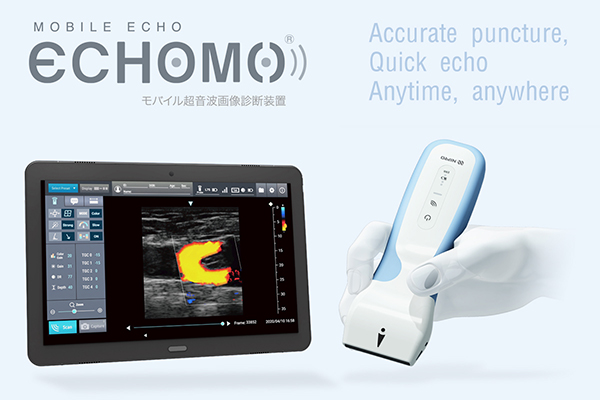

・モバイルエコー「ECHOMO™」

医療現場で求められる「スピーディで確実性の高い穿刺」をサポートするモバイルエコー「ECHOMO™」を紹介します。

タブレットの起動は,約15秒以内のクイックスタートが可能であり,プローブは連続3時間の使用が可能な設計です。

軽量・小型のリニアプローブから得られた情報は,10インチの大型タブレットに,高精細な画像で表示されます。

プローブとタブレット間はWifi通信でワイヤレス接続され,ケーブルの取り回しの煩わしさがありません。

使いたい場面で,使いたい時に,現場間の持ち回りもスピーディにおこなえるデバイスです。